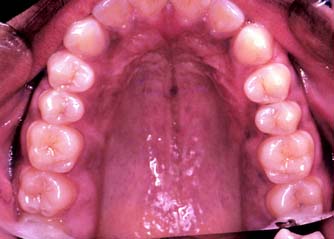

This class (Figs. 1-31 and 1-32) is characterized by substantially compromised location and extent of edentulous areas in both arches, abutment condition necessitating substantial localized adjunctive therapy, occlusal characteristics necessitating reestablishment of the entire occlusion without a change in the occlusal vertical dimension, and residual ridge conditions.

Fig. 1-32 Class III patient. The patient is categorized as Class III because large defective amalgam and composite restorations are present in four sextants. The remaining tooth structure is substantially compromised in most posterior teeth. The occlusion is substantially compromised, necessitating reestablishment of the occlusal scheme without a change in the occlusal vertical dimension. A, Frontal view, maximum intercuspation. B, Right lateral view, maximum intercuspation. C, Left lateral view, maximum intercuspation. D, Occlusal view, maxillary arch. E, Occlusal view, mandibular arch. F, Panoramic radiograph.

(From McGarry TJ, et al: Classification system for the completely dentate patient. J Prosthodont 13:73, 2004.)